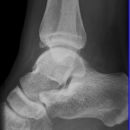

Sprunggelenk

Weber A

Weber B

Weber C + dorsales Volkmann

Trimalleoläre

Vorderes Volkmann + lat. Talusschulter